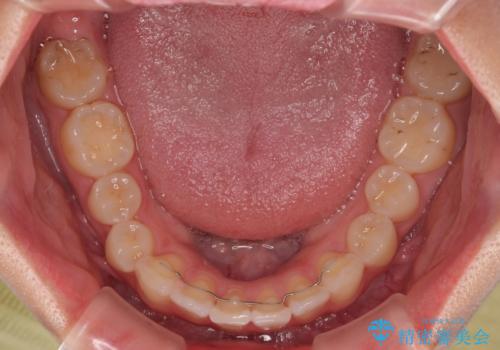

前歯の捻れを改善するとともに、口元が少しでも引っ込むように治療計画を立て、仕上げることができました。

長時間の装着を徹底し、遠方からの通院にもかかわらずしっかりと通院いただき、予想よりも早く治療を終えることができました。